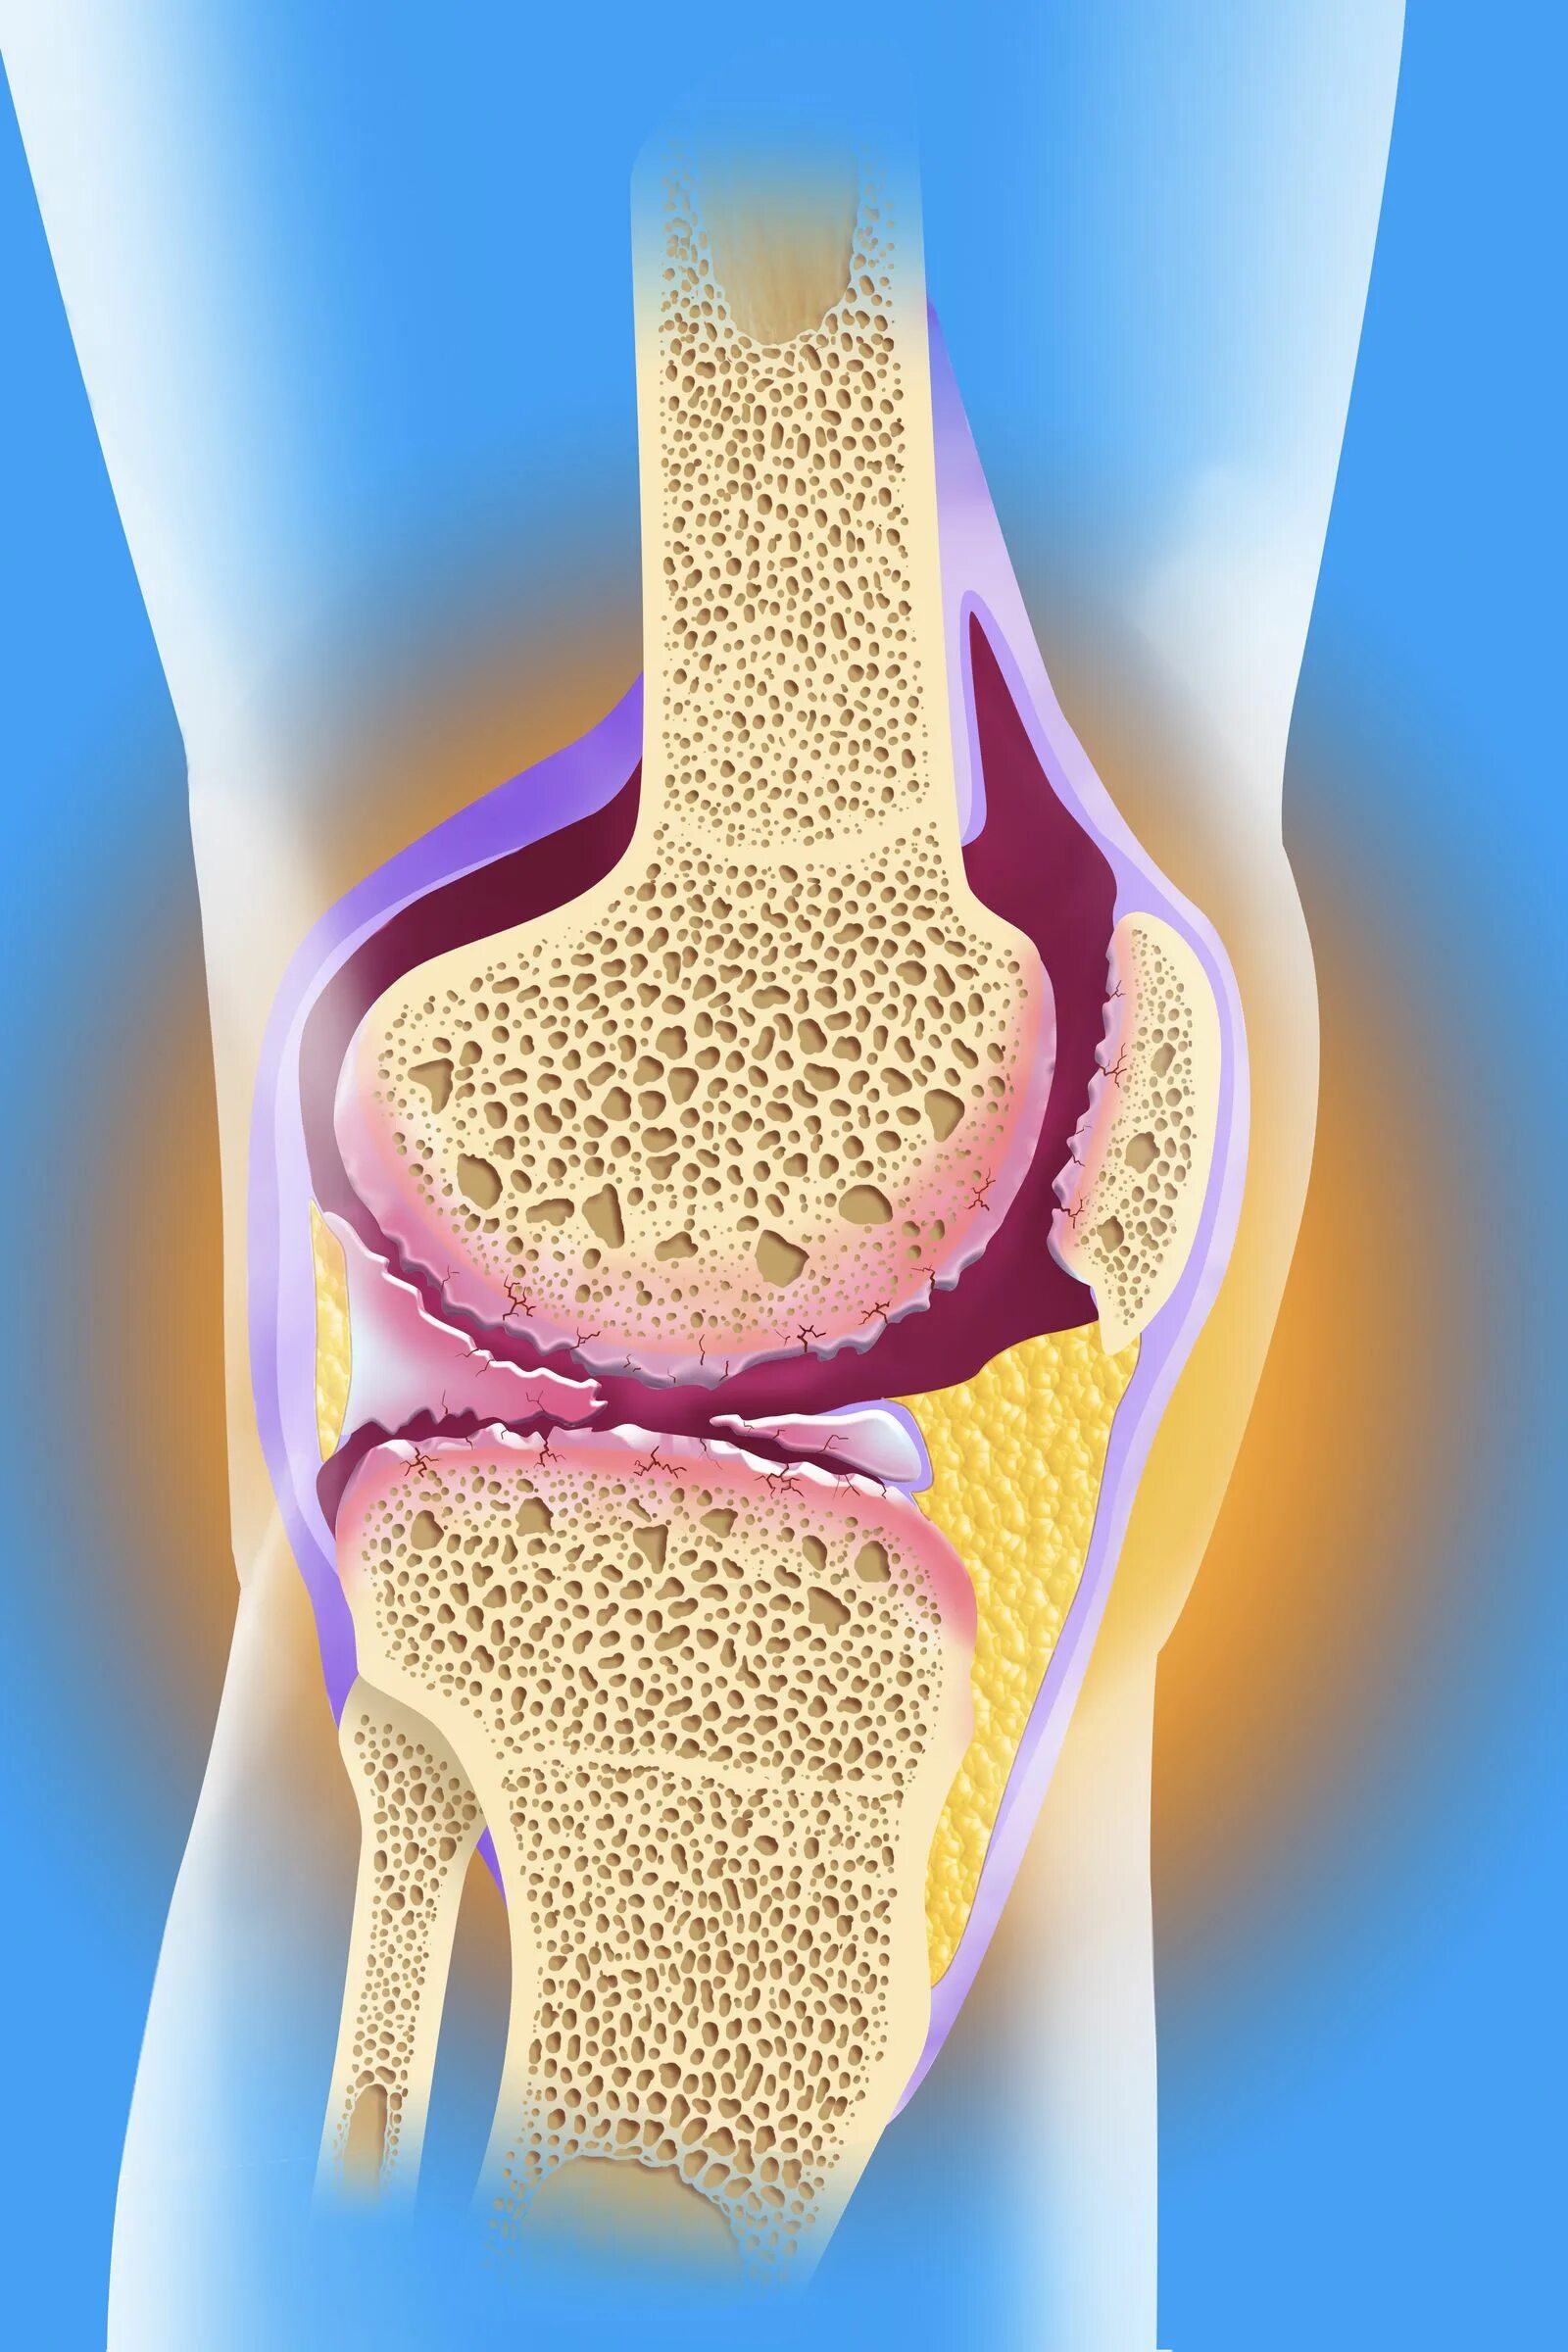

Болезнь соли в суставах